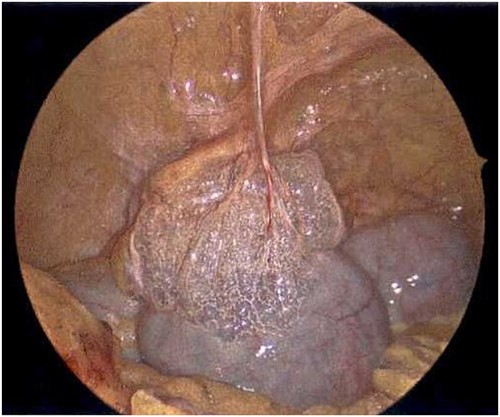

On Hospital Day 2, an interval CXR showed continued resolution of the right-sided pneumothorax but worsening subcutaneous emphysema of the bilateral chest wall and pneumoperitoneum (Fig. 3). Surgical consultation was sought, leading to diagnostic laparoscopy. In the abdomen, emphysematous changes within the gastrohepatic ligament and omental adhesions to the anterior abdominal wall were visualized (Figs 5 and 6). Laparoscopic exploration revealed no diaphragmatic injury or perforated viscera but identified emphysematous changes throughout the preperitoneal space, small and large bowel mesentery, and right paracolic gutter (Figs 7 and 8). Immediate post-op CXR no longer showed evidence of pneumoperitoneum (Fig. 4). The patient was transferred back to the ICU and extubated after three days on Day 5. After the removal of chest tube and transfer to a medical floor on Day 8, the patient developed aspiration pneumonia that was treated with antibiotics. She was discharged on Day 15.

Laparoscope of the large bowel revealing subserosal emphysema within the adventitia.